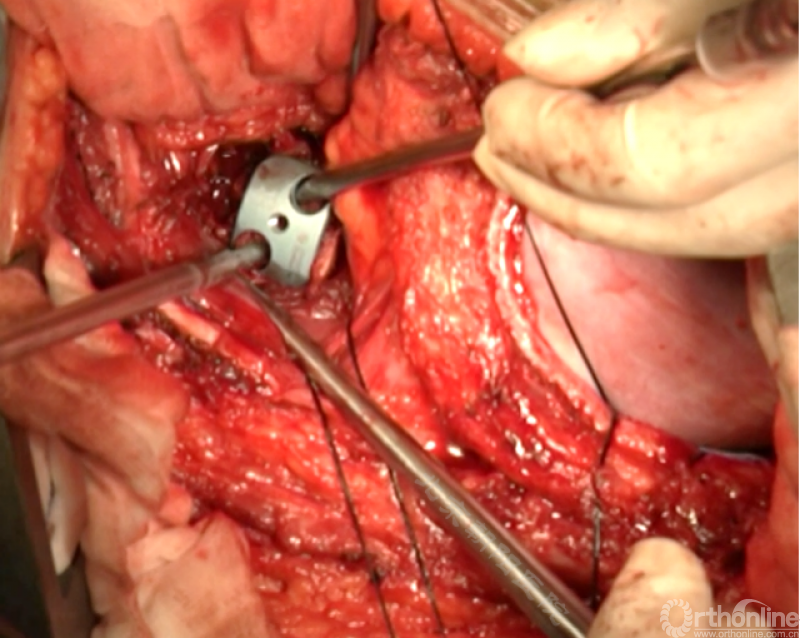

将预先折弯的金属棒先置入背侧。

椎间融合器经前方置入凹侧,确保腰椎前凸的恢复和冠状面畸形的矫正,将剩下的骨移植物置入椎间隙内。

置入腹侧金属棒。

使用双棒系统时先安装背侧的棒,可进行90°的去旋转,也可以直接通过前方螺钉矫正冠状面和矢状面的畸形,然后固定后方的棒,可进一步通过加压矫正冠状面畸形。

矫正后神经检测未见异常术中唤醒患者下肢活动良好,术中透视矫正效果满意、内固定位置良好。根据手术具体情况放置合适尺寸的横连接加强内固定。